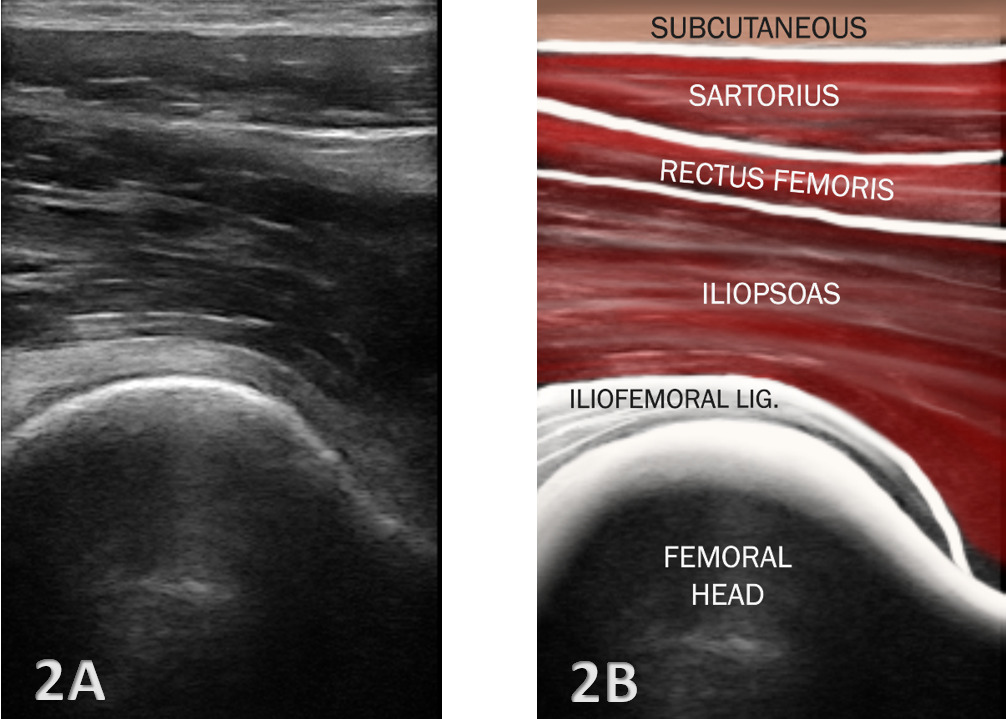

Proper patient positioning and transducer placement are crucial for visualizing the iliopsoas. The patient is typically positioned supine with the hip slightly externally rotated to improve access to the anterior hip region. A high-frequency linear transducer (7-12 MHz) is commonly used to visualize the iliopsoas complex. A curvilinear transducer may be necessary for deeper visualization.

Transverse Plane: The transducer is placed parallel to the inguinal ligament to identify the femoral vessels, then moved laterally to locate the iliopsoas muscle.

Longitudinal Plane: The transducer is aligned along the muscle fibers to assess the muscle and tendon continuity.

Normal Anatomy: The iliopsoas muscle appears as a hypoechoic (darker) striated structure with internal echogenic (brighter) fibrous septa typical of a muscle.12 The tendon is more echogenic and is best visualized near its insertion on the lesser trochanter.